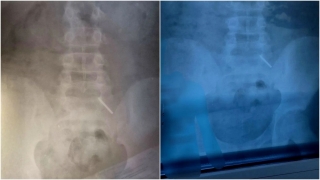

В Саратовской области два мальчика умудрились проглотить батарейки.

Пациенты двух и девяти лет поступили в Балаковскую городскую клиническую больницу.

Эндоскописты оперативно извлекли крупную батарейку из желудка школьника.

А у малыша инородное тело уже успели опуститься в кишечник, поэтому врачи и рентгенологи вели за пациентом пристальное круглосуточное наблюдение до благополучного разрешения ситуации.